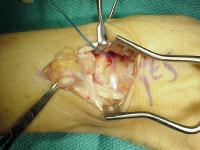

Complete scapholunate ligament disruption seen intraoperatively. A strip of extensor retinaculum is harvested as a ligament graft, left attached to the triquetrum. (Right hand, fingers to the right)

Case 2. Direct repair of scapholunate ligament and retinaculum  transfer (Ragnell retractor beneath). (Right hand, fingers to the right)

Case 3. Two strips were used, one to the distal scaphoid and one for a direct scapholunate segment. (Left hand, fingers to the right)

Retinaculum transfer. The screws were cut flush with the bone, ends barely visible here in the scaphoid and lunate. (Right hand, fingers to the right)